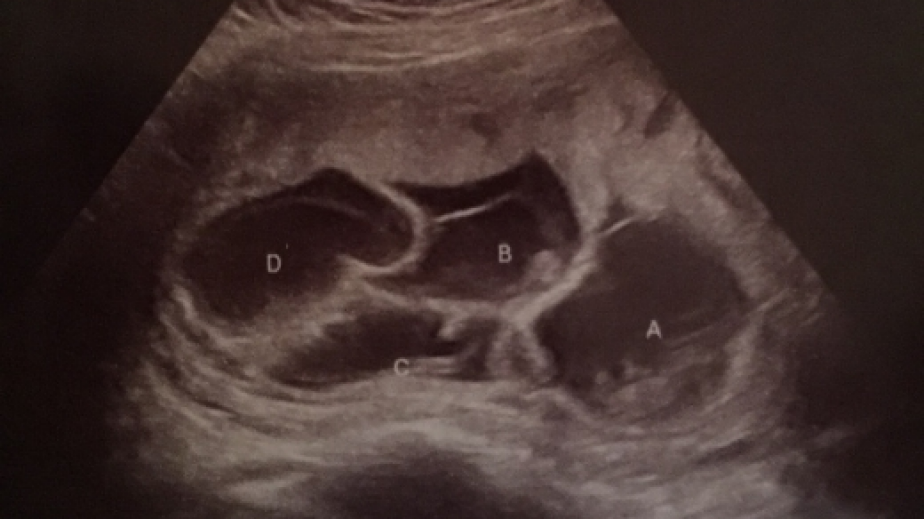

Съпрузи очаквали бебето си, но когато отишли на ултразвук, разбрали, че подобна бременност има едва една от 700 хиляди жени. Кайли и Филип искали много дъщеричката им да има братче или сестриче и затова се решили да имат още едно дете.

Когато дошло времето на първия ултразвук, настъпила истинска изненада. Двамата дори и не предполагали какво ги очаква, когато лекарят им показал нещо наистина рядко. Кайли била бременна не с едно, не дори с две, а с цели четири бебета.